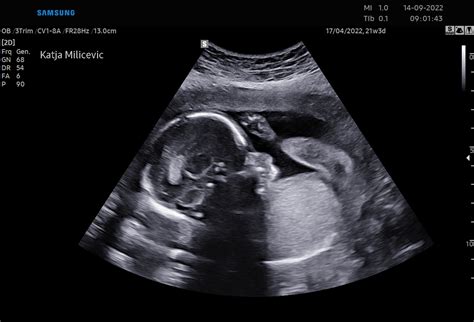

V 16. tednu nosečnosti plod meri približno 12 centimetrov in tehta okoli 20 gramov. Do konca drugega trimesesečja se pričakuje, da bo njegova velikost narasla na približno 36 centimetrov in teža na 650 gramov. V tem tednu so udja in sklepi že v celoti razviti, mišice se krepijo, otrok pa postaja bolj živahen v svojih gibih. Po telesu se začnejo pojavljati tanke dlačice, znane kot lanugo, rastejo pa tudi obrvi in trepalnice. Že v 13. tednu so znanstveniki opazili izrazito povečanje teže ploda, vse glavne mišične skupine pa se že odzivajo na dražljaje iz možganov. Plod lahko že upogiba roke v zapestju in komolcu ter stiska prste v pest. Obstaja možnost, da se že razvijajo pogojni refleksi, kar nakazuje na dokaj razvito možgansko skorjo, spomin in živčne poti, ki povezujejo organe in mišice.